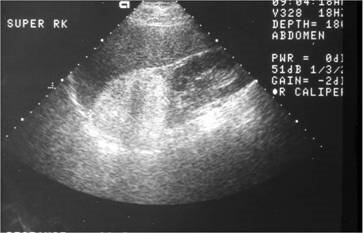

【108-1 醫學(五) 第72題】40歲男性病⼈因上腹部不適,上腹部超⾳波檢查發現右腎上⽅腫瘤如圖,最可能的診斷為何?

A adrenal myelolipoma B adrenal pheochromocytoma C adrenal cortical adenoma D adrenal cortical carcinoma

這題的解題核心在於辨識超音波影像中,腎臟上方腫瘤呈現的「高回音性」特徵,這是脂肪組織的典型表現,強烈指向腎上腺髓脂肪瘤。